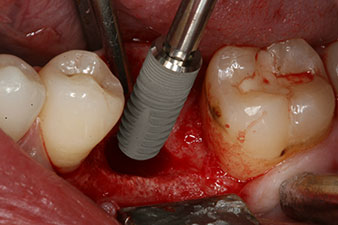

Das Drehmoment beim maschinellen Einbringen war 43 Ncm. Zusätzlich wurde, nach Einschrauben eines speziellen, auf das Implantatsystem abgestimmten Mess-Pfostens (SmartPeg), der ISQ-Wert mit der Sonde des W&H Osstell ISQ Modul bestimmt.

Dieses Modul ist für das Implantmed von W&H optional erhältlich und wird an den Implantologiemotor gedockt (vgl. Abb. 11). Der dimensionslose ISQ-Wert war direkt bei der Insertion 64 in oro-vestibulärer und 68 in mesio-distaler Richtung (Maximalwert = 100). Dies hätte eine offene Einheilung oder sogar Sofortversorgung erlaubt.

Wegen des unzureichenden Knochens krestal am Implantat wurde der Bereich mit den bei der Präparation des Implantatlagers gesammelten Knochenspänen augmentiert und speicheldicht vernäht.